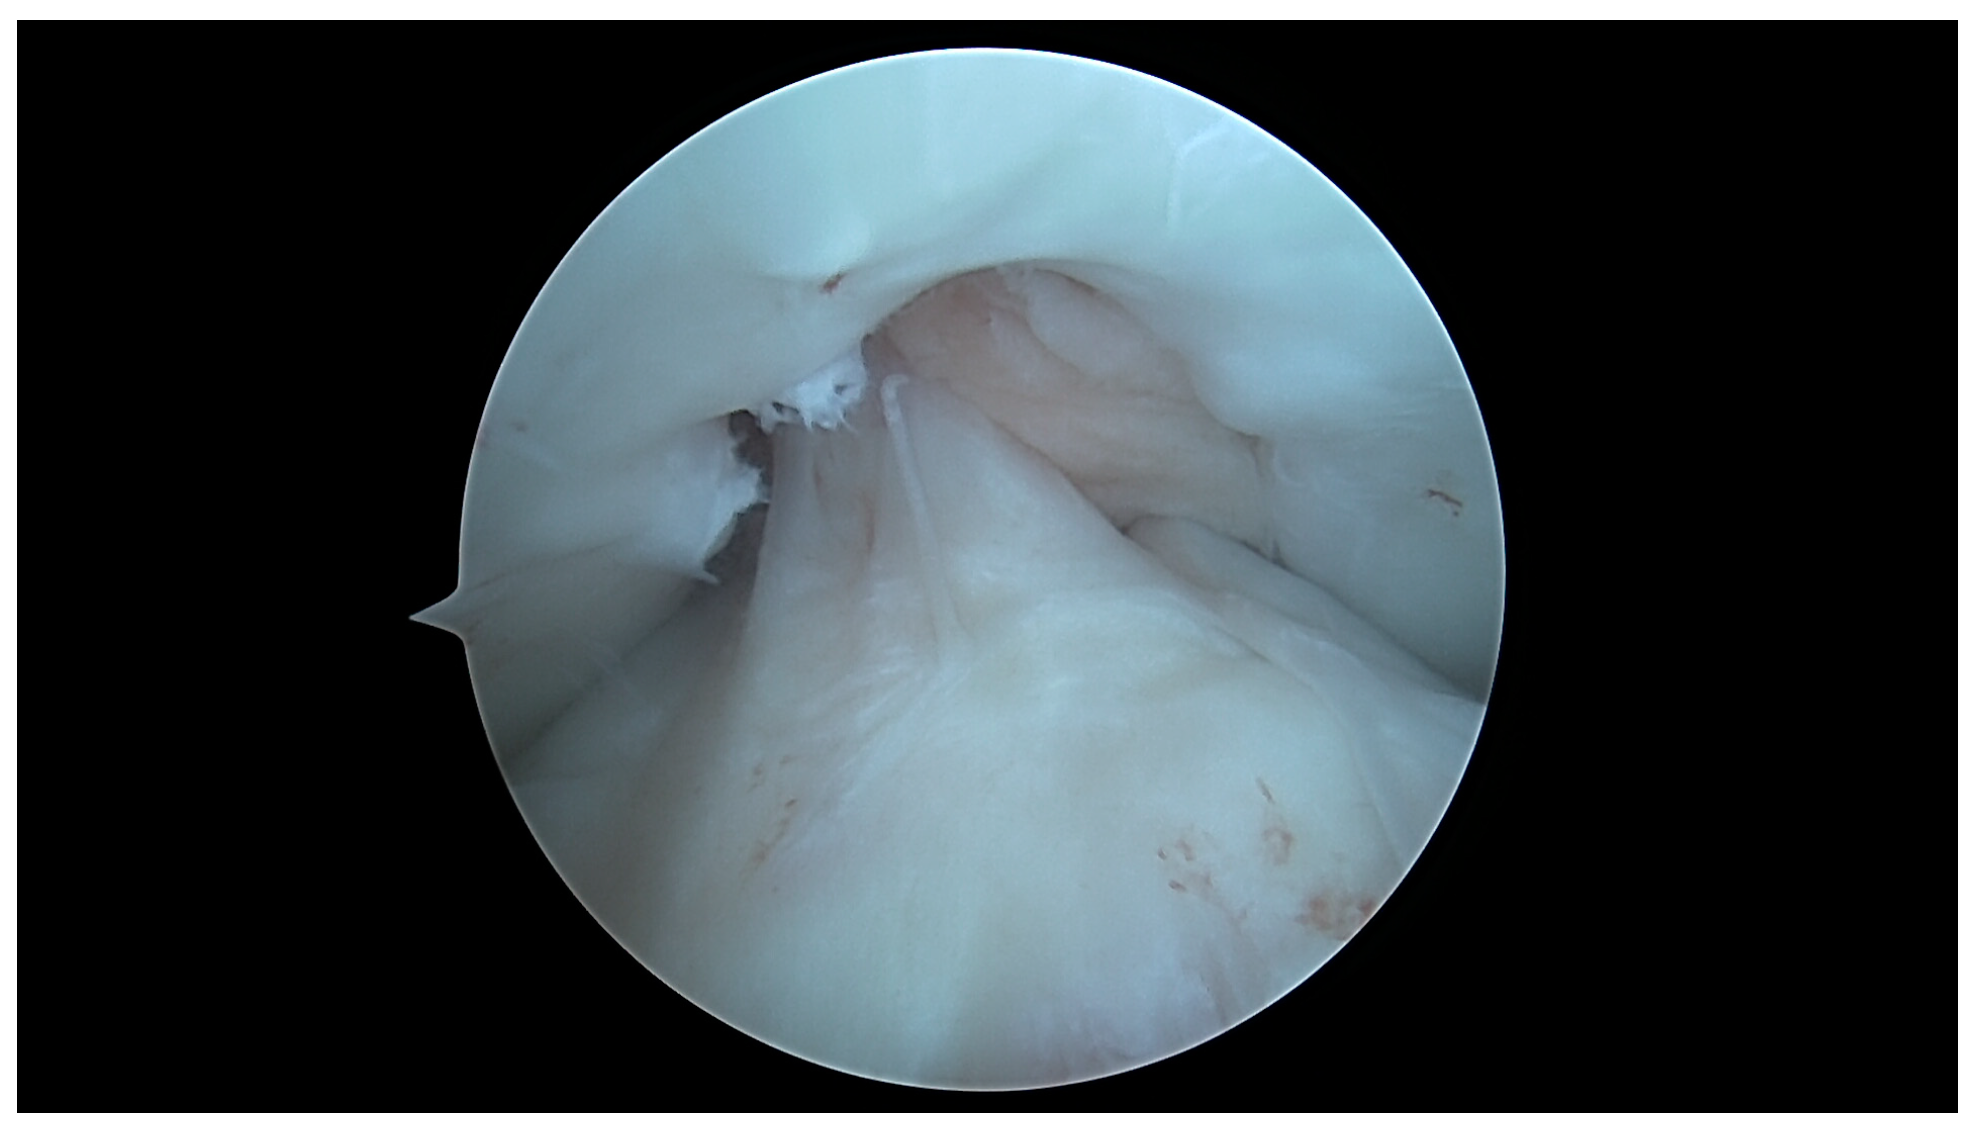

4.1. U-Shaped Notch

4.2. A/W Shaped Notch